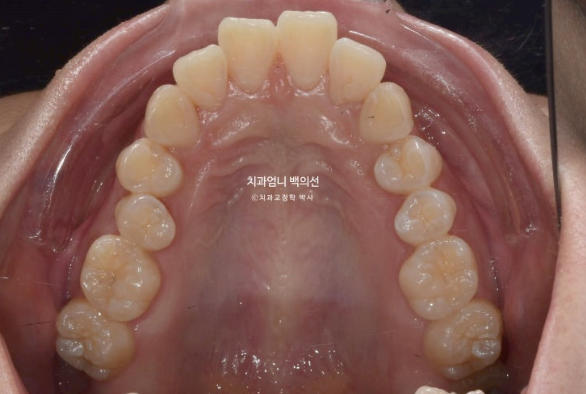

23년 3월부터 24년 5월까지 1년 2개월간 52개의 장치를 낀 후 재제작 당시의 모습 보여드리겠습니다.

과개교합은 잘 개선이 되었습니다.

발치공간이 아직 남아있고 앞니 각도의 개선이 더 필요합니다.

아래 어금니들은 사랑니 공간으로 잘 이동했습니다.

한달간 추가장치 제작기간을 기다려 24년 6월부터 두번째 세트의 장치를 끼기 시작했습니다.

25년 1월까지 7개월간 추가장치를 끼고 치료가 마무리 되었습니다.

개선된 과개교합과 일치된 중심선

앞니 뻗침도 많이 좋아졌습니다.

총 치료기간은 1년 11개월이고 실제 장치를 낀 기간은 1년 9개월입니다.